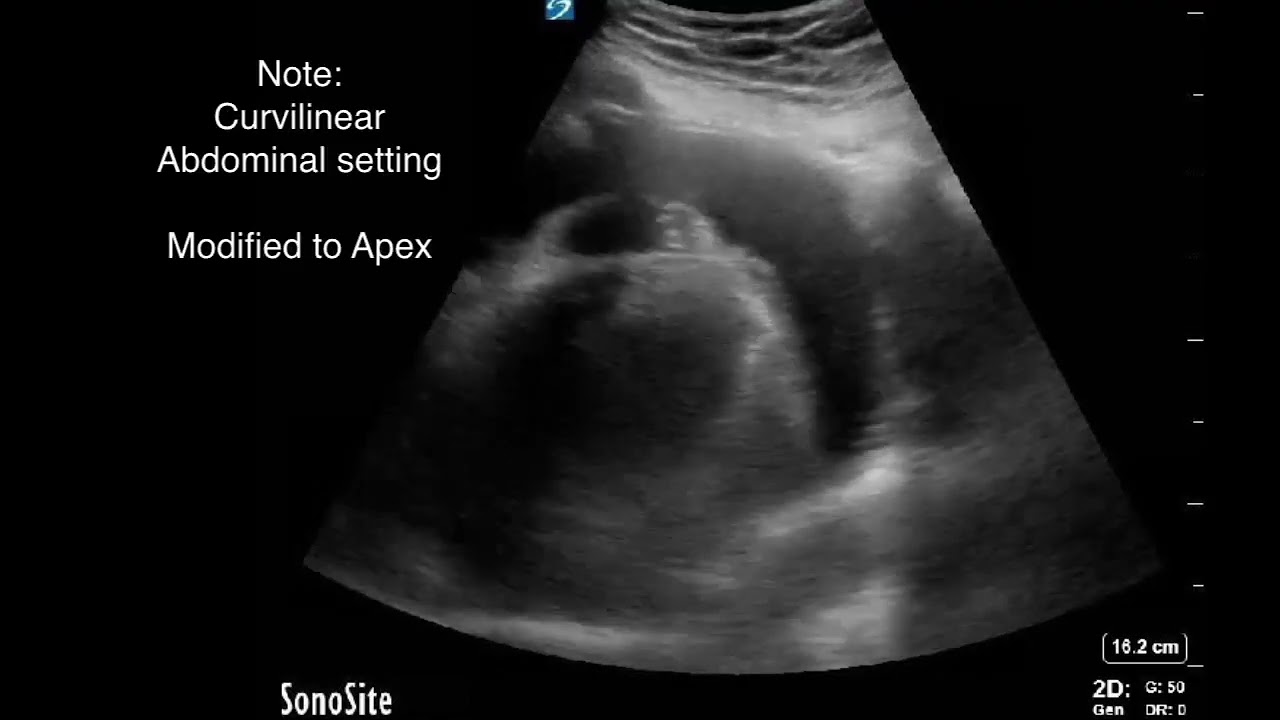

Скачать или смотреть Ultrasound Guided Pericardiocentsis and Drain Placement

Ultrasound Guided Pericardiocentsis and Drain Placement

How to perform a ultrasound guided pericardiocentesis, and the equipment you'll need to place a drain along with this.